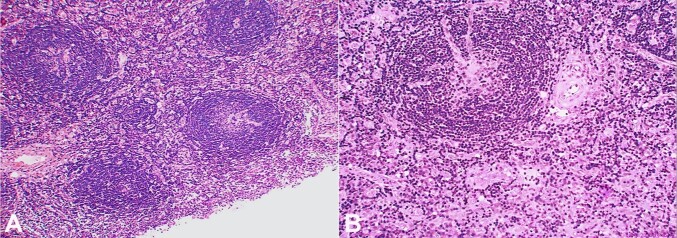

Castleman disease (CD) is a rare, benign lymphoproliferative disorder, mostly involving the mediastinal lymph nodes, but can occur wherever lymphoid tissue is found. With only a few published case reports, there needs to be more literature on its cytological findings. We report the case of a 63-year-old female presenting with left upper cervical swelling. Fine needle aspiration cytology smears showed variably sized lymphoid follicles with diminished germinal centers, prominence of follicular dendritic cells, and capillaries traversing some of the follicles. The possibility of a hyaline-vascular type of Castleman disease was suggested. Histopathology confirmed the cytological diagnosis. The index case is being presented to discuss the cytological features of the CD along with its histological and immunohistochemical correlation.